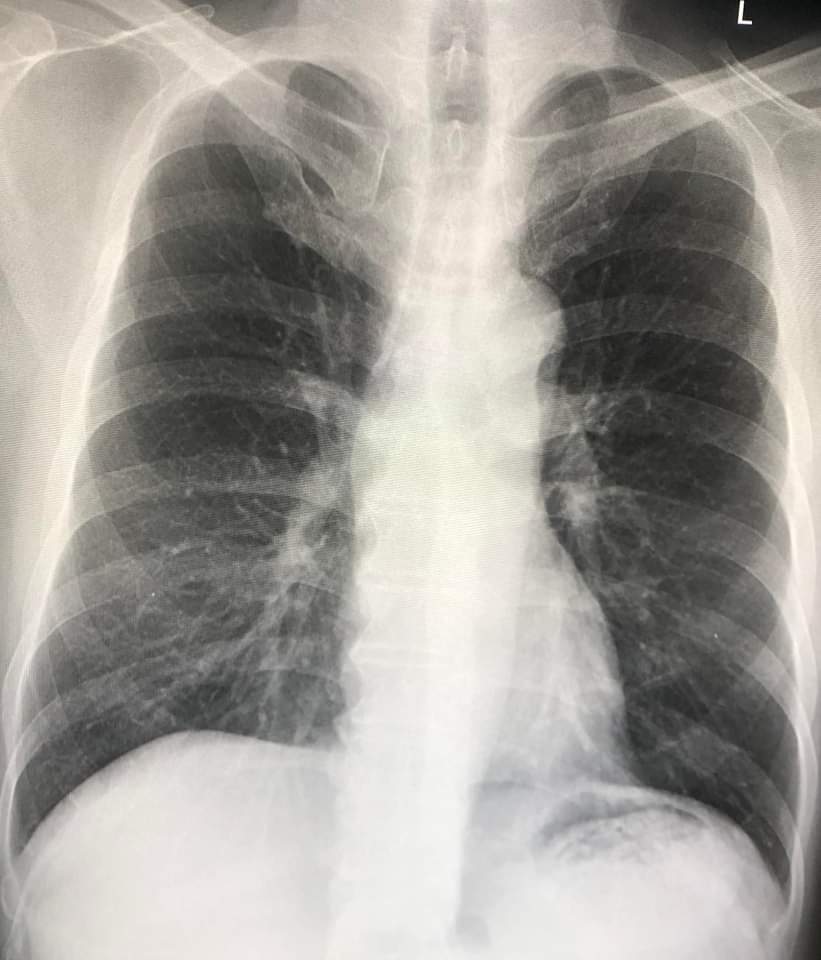

ผู้ป่วยหญิงอายุ 89 ปีเป็นโรคความดันสูง เบาหวาน หัวใจเต้นผิดจังหวะ ได้รับวัคซีนแอสตร้าเซเนก้าครบ 2 เข็ม มา รพ.ด้วยไอ น้ำมูก ตาแดง 3 วัน ไม่มีไข้ ไม่ปวดหัว ไม่ปวดตัว จมูกได้กลิ่น ลิ้นได้รส แยงจมูกตรวจรหัสพันธุกรรม RT-PCR พบไวรัสโควิด-19 ปริมาณมาก เอกซเรย์ปอดปกติ

เนื่องจากผู้ป่วยรายนี้อายุมาก มีโรคประจำตัวหลายโรค มีความเสี่ยงที่เชื้อไวรัสโควิดจะลงปอด จึงตัดสินใจให้ยาโมโนโคลนอลแอนติบอดี REGEN-COV (Casirivimab and Imdevimab) หยดทางเส้นเลือด 1 โดส และไม่ให้ฟาวิพิราเวียร์ หลังได้รับแอนติบอดี ผู้ป่วยสบายดีตลอด อาการดีขึ้น ติดตามเอกซเรย์ปอดปกติ